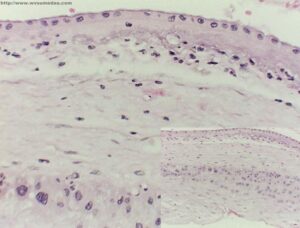

Sezione membrana amniotica

(ANSA) – MILANO, 11 GIU – Dallo strato piu’ interno della placenta umana, chiamato membrana amniotica, si puo’ ricavare materiale utile per riparare le cornee dei bambini danneggiate da traumi o infiammazioni. E’ una delle novita’ che gli esperti stanno discutendo al convegno nazionale della Societa’ di oftalmologia pediatrica (Siop), che si e’ aperto oggi a Milano. La membrana amniotica, spiegano infatti i ricercatori, fornisce elementi nutritivi che migliorano il decorso dei processi infiammatori che possono colpire la cornea. Tra gli altri temi su cui si concentrera’ il convegno ci sono le malattie oculari legate a disfunzioni del metabolismo, cosi’ come le nuove tecniche di diagnosi precoce e di riabilitazione visiva. ”Queste patologie – spiega Elena Piozzi, direttore dell’oculistica pediatrica all’ospedale Niguarda di Milano – sono piu’ frequenti nell’adulto, ma nel bambino sono molto piu’ gravi, perche’ qualsiasi tipo di intervento in eta’ infantile va supportato da un’adeguata attivita’ di rieducazione visiva, con tempi di recupero piu’ lunghi e maggiori costi sociali. Inoltre la vista e’ il primo canale di apprendimento, quindi piu’ sono gravi e precoci questi disturbi tanto maggiore e’ la probabilita’ di avere un ritardo psicomotorio”.